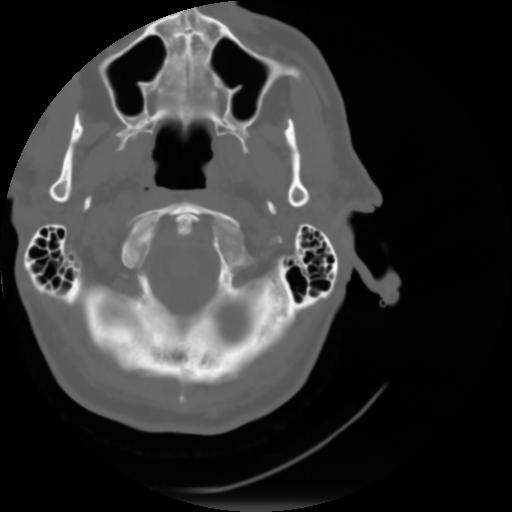

3 CEREBRO,,Axial,3.0,CEREBRO,,